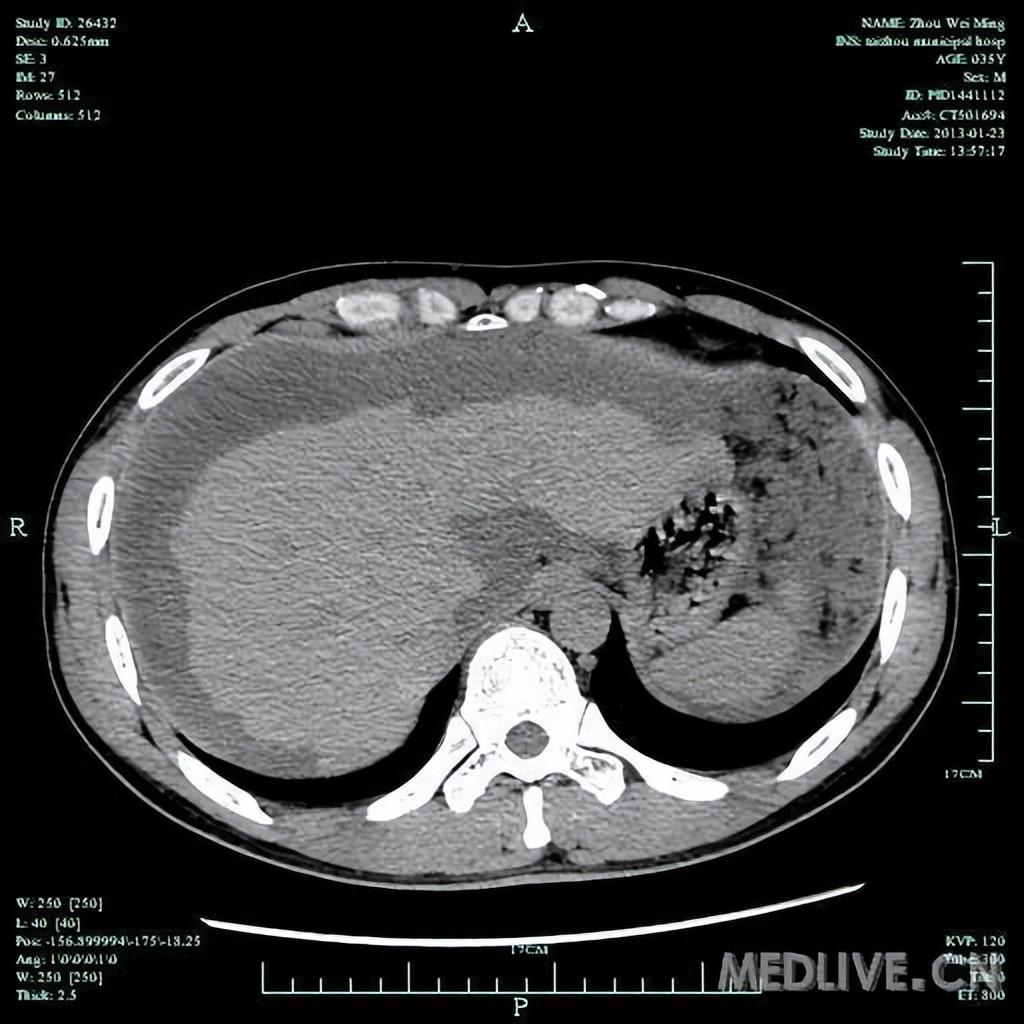

Image